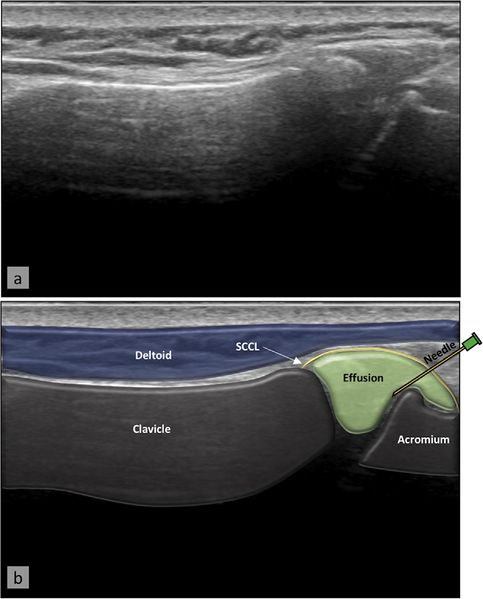

Acromioclavicular joint injection. The needle is inserted at the mid-line of the lateral edge and parallel to the probe, allowing it to be visualized entering the acromioclavicular joint. US image (a) with superimposed anatomy (b). From Plomb-Holmes et al., with permission.